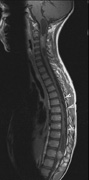

1. Schwannomas most commonly affect the fifth cranial nerve (CN), but any cranial nerve may be affected. In contrast to vestibular schwannomas (CN VIII), these typically do not grow large.84,90 Vestibular schwannomas (acoustic neuromas) are the classic finding in NF2 (Fig. 7). The risk for malignant transformation is low, but may be higher with radiation exposure.84,94

3. Other tumors: low-grade ependymomas and gliomas may affect the cervical spine and Brainstem (Fig. 7).84

Fig. 7. Neurofibromatosis type 2: Images of a 12-year-old boy with deafness and weakness in his arms and legs, whose father has bilateral deafness. Axial T2-weighted (a) and postcontrast axial (b) T2-weighted images reveal bilateral vestibular schwannomas, which are also known as acoustic neuromas (arrows). This is the classic finding of NF2. (b, c) Bilateral schwannomas are seen in Meckel's cave (arrowheads) and a (d) lower left cranial nerve schwannoma extends into the pars nervosa of the jugular foramen (arrow). (e) A part cystic and part solid enhancing ependymoma in seen within the cervical cord and medulla and within the distal cord and conus. (e, f) Thoracic schwannomas are present at numerous levels (arrowheads). Marked enhancement and thickening of the roots within the cauda equina also represent multiple schwannomas.